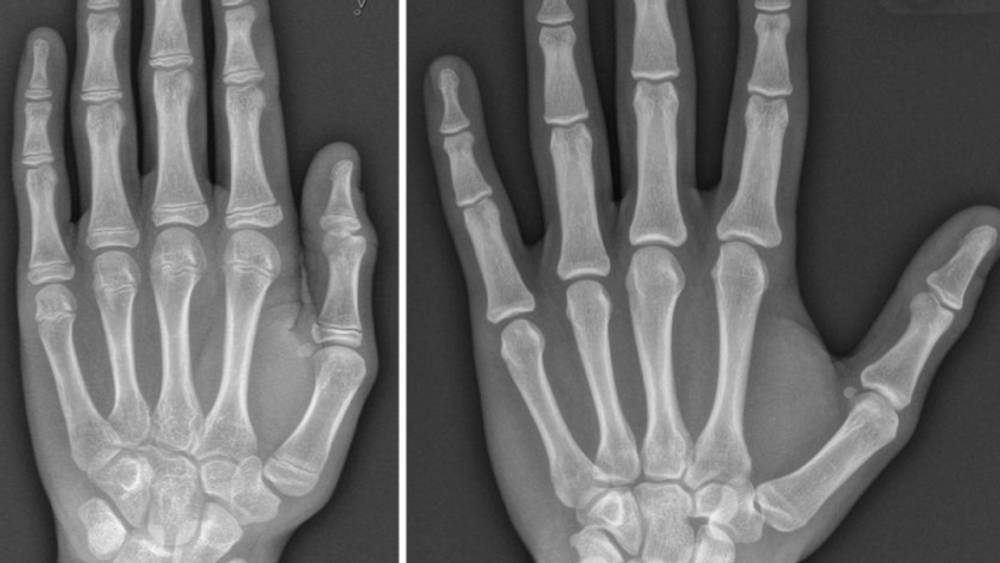

Utlendingsdirektoratet (UDI) vil avdekke om asylsøkerne er så unge som de oppgir at de er. For å sjekke asylsøkernes alder på best mulig måte, trengs to røntgenbilder; et av tenner og et av hånden. De siste fire årene har det vært umulig for UDI å bruke en slik dobbel, anbefalt kontroll, for Legeforeningen har bedt alle sine medlemmer om å boikotte forespørsler om alderstesting av asylsøkere. (HRS)